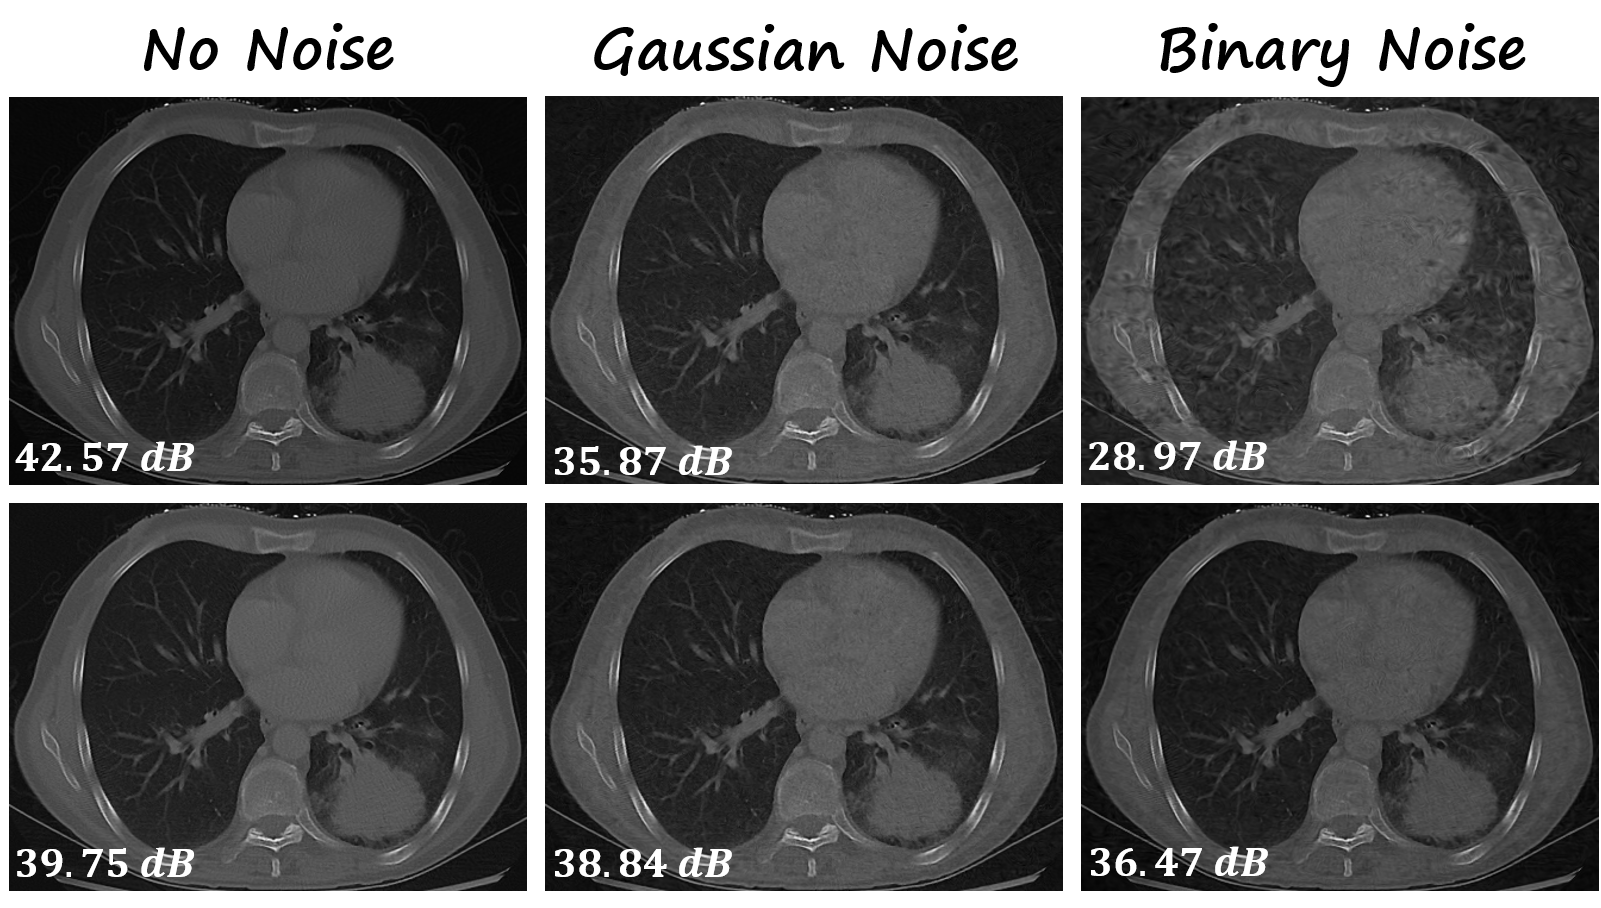

Figure 5: Reconstruction comparison of baseline SIREN (first row) and our method (second row) for CT image reconstruction under Gaussian and binary noise conditions.

More modality results. To demonstrate the generalization capability of our proposed method, we conduct more experiments across multiple modalities, including medical computed tomography (CT) image in Figure 5, audio in Figure 6 and video in Figure 7 [26, 27]. In Figure 5, the baseline SIREN outperforms our approach by 2.82 dB in the absence of noise, but our method are more robust under noise conditions by yielding up to a 7.5 dB in PSNR value. For audio signal reconstruction, a similar trend can also be observed: the reconstruction of our method is 8.04 dB lower than that of the vanilla SIREN model but achieves a PSNR increase of up to 2.84 dB under Gaussian noise and 2.93 dB under binary noise. For video reconstruction, as shown in Figure 7, we conduct an experiment on a 2-second video with 25 frames per second. As expected, our method excels in noisy environments, delivering a PSNR increase of up to 0.26 dB under Gaussian noise and 1.74 dB under binary noise. All the above experiments demonstrate that our method can effectively enhance the robustness of INRs in various applications.